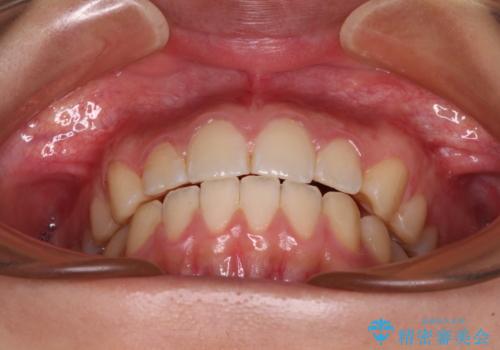

奥歯の咬み合わせを改善しながら、並行してインビザラインで歯列を整えることとしました。

カリエールディスタライザーを併用したことで、確実かつ短期間で治療を終えることができました。